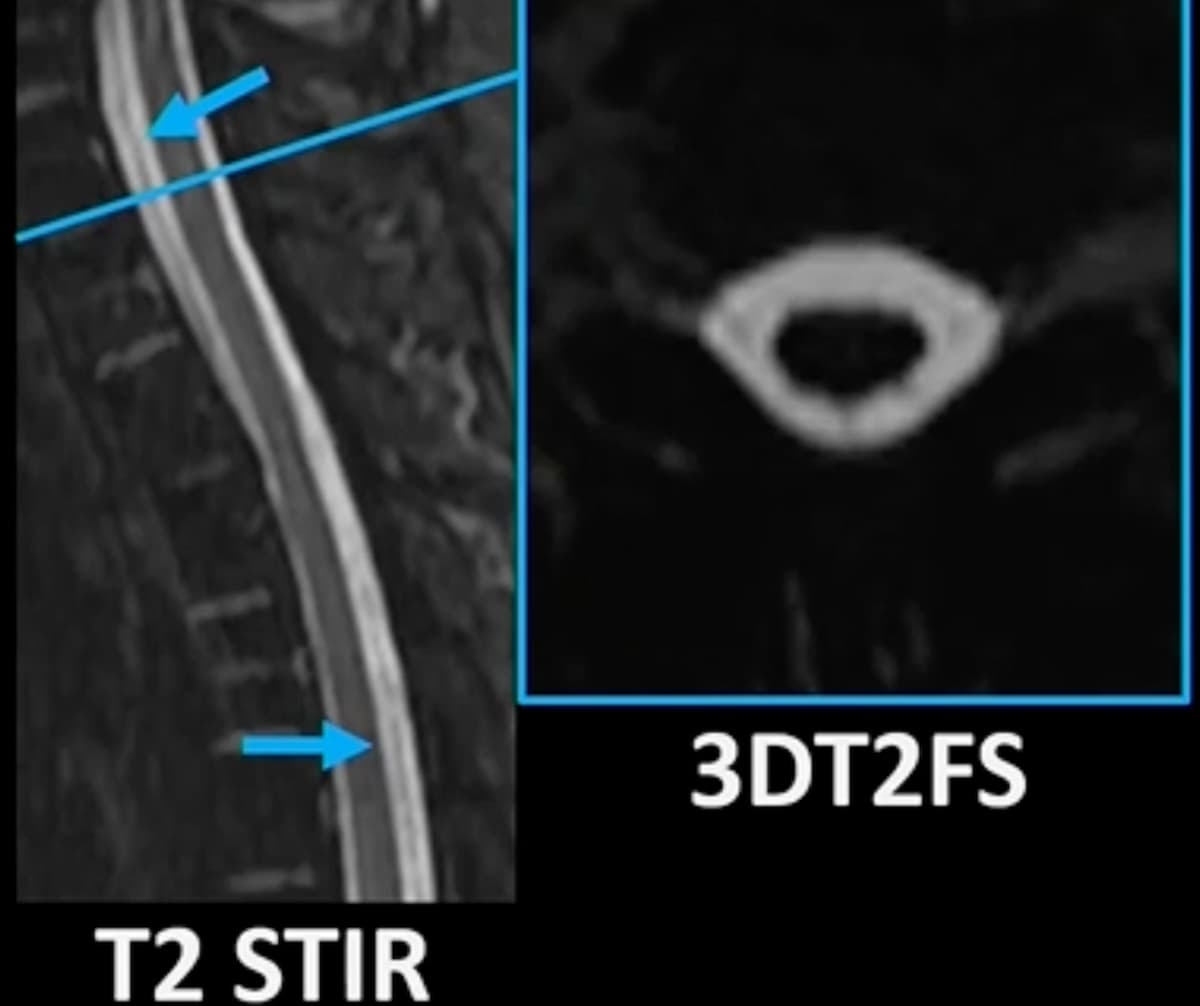

Given the increasing prevalence of breast reconstruction, researchers discussed key signs of common complications on magnetic resonance imaging (MRI), ultrasound and other imaging during a recent presentation at the American Roentgen Ray Society (ARRS) 2023 Annual Meeting in Honolulu, Hawaii.